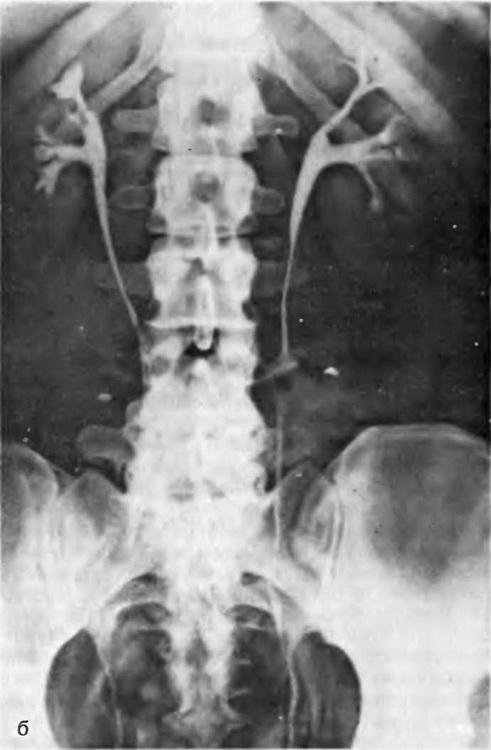

Ендометріоз сечоводів. Дана локалізація захворювання за своєю значимістю надзвичайно серйозна, оскільки може спричинити за собою стенозування сечоводу (рис. 15), розвиток гідро-уретера, гидропиелонефроза і втрату нирки.

При стенозірованіі нижнього відділу сечоводу ендометріозом по мірі розвитку патологічного процесу порушується перистальтика його; він розширюється і подовжується, виникають перегини його в різних відділах, в тому числі і у верхній третині. На урограмах може бути виявлено зовнішню схожість із змінами, описаними Остлингом. При рентгенологічному обстеженні апаратом з електронно-оптичним перетворювачем диференціювання не викликає труднощів з урахуванням сталості зображення при хворобі Остлинга і мінливості картини при наявності перешкоди до відтоку сечі в нижньому відділі сечоводу. Крім того, після усунення перешкоди до відтоку сечі хірургічним шляхом (уретеролиз, резекцію рубцево-зміненої непериста л ьтирующей частини сечоводу та/або неоуретероцистостомия) эктазия сечоводу і його перегини зазнають регресу.